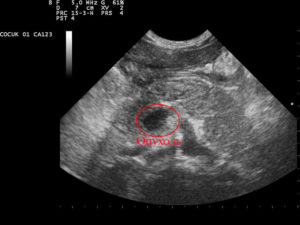

Почки Анэхогенные образования почек свидетельствуют о том, что они содержат кисту. Она всегда анэхогенна, имеет тонкие стенки и ровные границы, а также всегда круглой формы. При поликистозе почек таких образований всегда много. Почки при этом увеличиваются в размерах.

Из-за воспалительных патологий, а также некоторых видов нефропатий возникают образования с неоднородной эхогенностью. Обычно такое заключение врача-сонолога говорит о необходимости дальнейшей диагностики.

Возможно наличие анэхогенного образования и около почки. Это – признак околопочечной гематомы. Очертания органа при этом сохраняются.

Чрезкапсульный разрев почки: а- околопочечная гематома.

Наконец, наличие эхонегативного образования в почке говорит о наличии в ней раковой опухоли. Как правило, контуры такого образования нечеткие. Такие же контуры имеют почечные абсцессы.